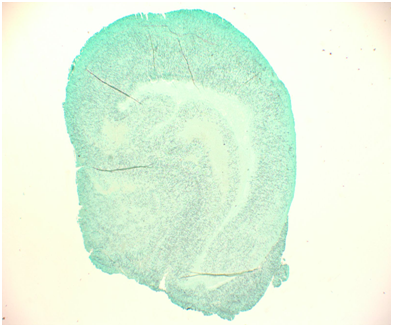

A 57-year-old white male patient with known history of coronary artery disease, morbid obesity, obstructive sleep apnea, hypertension, hyperlipidemia, atrial fibrillation, and tobacco use, presented to a local emergency room with a sudden sharp right arm pain, followed a few hours later by numbness of the right hand. His physical exam was normal except for a very weak pulsation of the right brachial artery. His initial workup included a normal chest x-ray with no acute cardiopulmonary process. A doppler ultrasound of the right upper extremity indicated thrombosis with near-complete occlusion of the distal right brachial artery. He was urgently seen by vascular surgery and underwent thrombectomy of the distal right brachial artery thrombus that was sent for pathology. Hematoxylin Eosin stain and Grocott’s methenamine silver stain showed fungal organisms identified at the thrombus, that had thin septate hyphae with regular branching and that were morphologically consistent with Aspergillus species (Figures 1-6). Subsequently, he was started on intravenous voriconazole, after his EKG, liver function tests were evaluated revealing a normal QTc interval, and liver enzymes respectively. Patient was then evaluated for evidence of disseminated Aspergillosis. His blood cultures have been negative. Aspergillus galactomannan antigen was negative, and his HIV ½ Antibody screen was negative. A computed tomography (CT) scan of the chest with angiography showed an ascending aortic pseudoaneurysm with large soft tissue component, representing a mycotic aneurysm. The contrast opacified lumen of the pseudoaneurysm measured 2.8 x 3.8 cm and there was a portion of the pseudoaneurysm more superiorly that was thrombosed measuring 6.3 x 7.2 cm (Figures 7 & 8). His lungs were clear without evidence of pulmonary nodules or consolidation. CT scan of the brain with contrast and a complete ophthalmological examination were unremarkable. Transthoracic and transesophageal echocardiograms showed no major cardiac finding and no evidence of valvular vegetations. He was then transferred to a tertiary care center where he underwent a homograft of cryopreserved human tissue given the fact that he has an infected mediastinum. He was continued on Voriconazole orally, and he will receive it for life.To note that, five years prior to this event, he underwent an urgent coronary artery bypass grafting (CABG)X3 with reversed autogenous saphenous vein graft from the aorta to the left anterior descending artery, from the aorta to the ramus intermediate, from the aorta to the obtuse marginal artery, along with endoscopic vein harvest left and right greater saphenous veins (from knee to groin bilaterally).

Figures 1-3 Hematoxylin-Eosin stain showing thin septate hyphae with regular branching.

Figures 4-6 GMS stain showing the same findings.